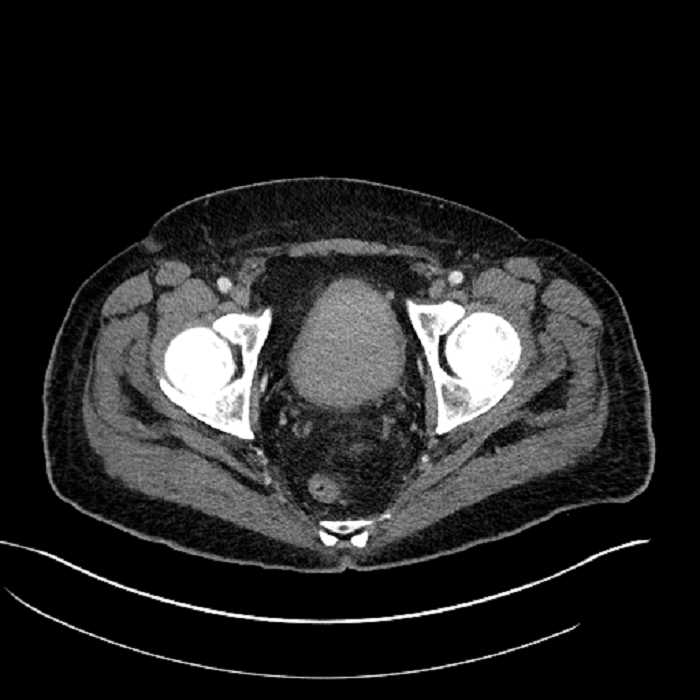

Age: 63

Sex: Male

Indication: Abdominal pain

• High grade stenosis of the left common iliac artery, with the left internal and external iliac arteries remaining patent

Acute sigmoid diverticulitis complicated by a small contained perforation and a large abscess in the right hepatic lobe. Additional small subcapsular abscesses along the anterior margin of the left hepatic lobe.

High grade stenosis of the left common iliac artery. The left external and internal iliac arteries are patent.

Hepatic abscess showing the double target sign with low density internally surrounded by a thin inner enhancing rim (red arrow) and ill-defined outer low density rim (yellow arrow). Blue arrow indicates an internal septation. Red arrows: additional smaller subcapsular abscesses. Red arrow: focal contained perforation associated with diverticulitis.